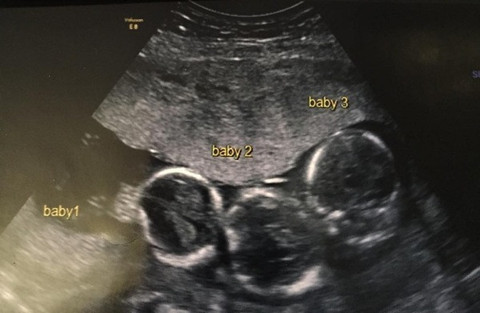

Galerinin tamamı için tıklayınızAile kızlarına kardeş istiyordu ancak üçüzleri olacağını tahmin edemediler. Hamileliğinin ilk haftalarında Becki-Jo hastalandı ve başı ağrımaya başladı. Ultrasona girince üçüzleri olacağını öğrendi. Becki-Jo, Liverpool Echo’ya “Hayatımın en büyük sürpriziydi! Sülalemizde üçüzleri olan kimse yok. Haliyle çok şaşırdık” dedi. Hamileliğinin 31. haftasında Becki-Jo sezaryenle Roman, Rocco ve Rohan’ı dünyaya getirdi. Bebeklerin her biri 1.5 kiloydu ve altı haftalarını yoğun bakımda geçirdiler.